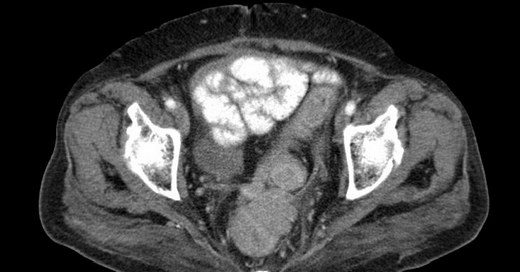

Yumuşak doku kanseri neden olur. Eğer midenizde yumuşak bir doku sarkomu gelişirse çok büyük olana ve diğer yapılar üzerinde basıncaya kadar keşfedilemeyebilir. Sarkomlar kemiklerde kaslarda tendonlarda sinirlerde kıkırdakta yağ dokusunda veya kan damarlarında meydana gelebilir. Yumuşak doku kanserinde risk faktörleri nelerdir. Bu dokularda meydana gelecek olan herhangi bir bozukluk yumuşak dokunun tamamen olumsuz etkilenmesine neden olur.

Yumuşak doku kanserinin en sık görülen belirtilerden biri yumru veya kitle oluşumudur. Kol ve bacaklarda tümör oluşumları ile kendini gösteren yumuşak doku kanseri çocukluk ve gençlik çağındaki tüm kanser hastalıklarının yaklaşık 6 6 sını oluşturuyor. Sarkom bağ dokusundan kaynaklanan ve nadir görülen bir kanser türüdür. Yumuşak doku kanserinin olası belirti ve semptomları.

Yumuşak doku tümörleri kanseri neden olur. Kanser riskini artıran bazı sendromlar ebeveynlerden çocuklara geçebilir. Kolunuzun veya bacağınızın derisi altında ağrısız bir topak veya kitle yumuşak doku sarkomasının ilk belirtisi olabilir. Sarkom vücudun herhangi bir yerinde kemik veya yumuşak doku gibi başlayabilir.

Yumuşak doku sarkomları veya yumuşak doku tümörlerinin meydana geliş nedeni henüz tam olarak bilinmemektedir. Yumuşak doku kas dokuları tendonlar cilt altı ve bağlar gibi hayati dokuları kapsar. Sarkom yunancada etin büyümesi anlamındaki sözcükten geliyor yumuşak doku sarkomları vücutta yumuşak dokularda baş gösteren kanserli habis tümörler. Hastalık ilk evrelerinde genellikle hiçbir belirti göstermiyor ancak tedavide.